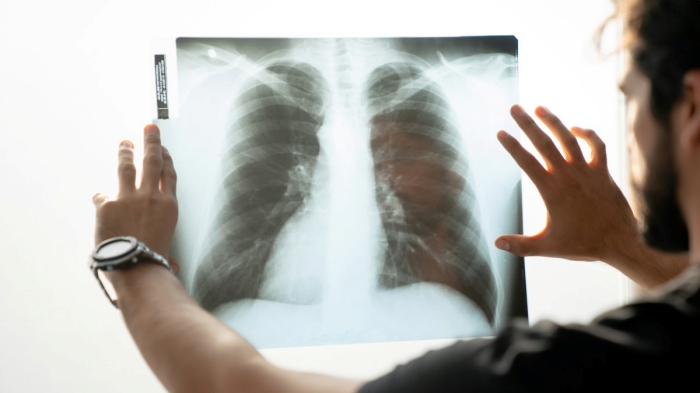

인간의 의사에 있어서는, 피부색 등을 알 수 없는 엑스레이 사진으로 환자의 인종을 구분하기는 어렵지만, 새롭게 의학지 The Lancet Digital Health에 발표된 논문에서, "AI는 흉부 엑스레이 이미지를 통해 인종을 90%의 정확도로 구분할 수 있다"는 것으로 나타났다.

우선 연구팀은, 엑스레이나 CT 스캔으로 촬영된 의료용 흉부 엑스레이 이미지에, 피험자의 자진 신고를 토대로 "백인", "아시아인", "흑인" 중 하나의 라벨을 붙인 데이터셋을 사용해 AI를 훈련. 데이터셋의 화상에는 피부색이나 머리의 질감 등 인종을 나타내는 분명한 지표는 포함되지 않았다는 것.

그리고, 대량의 인종 라벨이 달린 이미지로 훈련한 AI에 대해, 이번에는 라벨이 붙어 있지 않은 다른 흉부 에스레이 이미지를 통해 인종을 판별시켰다. 그랬더니 AI는 90% 이상의 정확도로 엑스레이 이미지에 찍힌 인종을 백인, 아시아인, 흑인 중에서 식별하는데 성공.